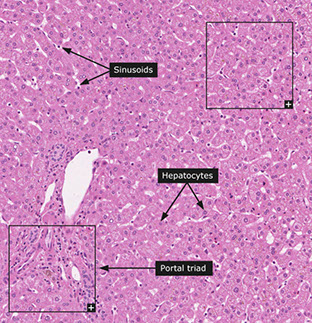

Histology

Broken into hepatic lobule (2D) or acinus (3D), where the hepatic lobule has central venule with hepatocyte cords radiating to peripheral portal tracts

Portal Tracts

Contain hepatic artery, portal vein, and bile duct

- hepatic artery is normally about the same diameter as the bile duct, and are seen together most of the time, while the portal veins have ~5x the lumen diameter

Lobules

Made of cords (plates) of hepatocytes usually 2-3 cells thick

Lobes divided into zones based on proximity to normal structures

- Zone 1: hepatocytes around portal tracts (these cells have more rich O2 and nutrient supply than zone 3)

- Zone 2: cells not in zone 1 or 3

- Zone 3: hepatocytes around the Central vein (C=3) and are important in detoxification

Central vein

vary in size (larger at hilum, smaller at periphery of liver), which corresponds to the thickness of the wall